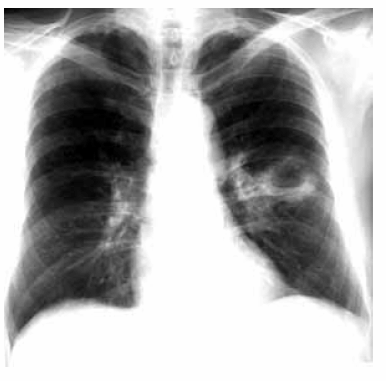

Um homem de 40 anos de idade queixa-se de tosse produtiva, com duração de 14 dias, com grande quantidade de catarro mucopurulento e fétido. Relata que a quantidade de catarro aumentou nos últimos 2 dias e que ele passou a apresentar vários episódios de febre. Informa ser etilista pesado por vários anos e tabagista de 1 maço de cigarros por 25 anos e nega doenças prévias. Antes de procurar o hospital, ele foi a um posto de saúde, há 1 semana, onde foi submetido a exames para tuberculose, que foram negativos, e como não melhorasse, fez uso, por conta própria, de um comprimido de antibiótico (não se lembra do nome), há 1 dia. Ao exame clínico, apresentou sinais vitais normais, péssimas condições de higiene oral e dentária (várias cáries). Ritmo cardíaco regular, sem sopros. ausculta pulmonar, havia redução do murmúrio vesicular no terço médio do hemitórax esquerdo. Exames laboratoriais evidenciaram leucocitose moderada, com contagem diferencial normal, sem outras alterações. O exame radiográfico do tórax na projeção póstero-anterior é apresentado na figura abaixo.